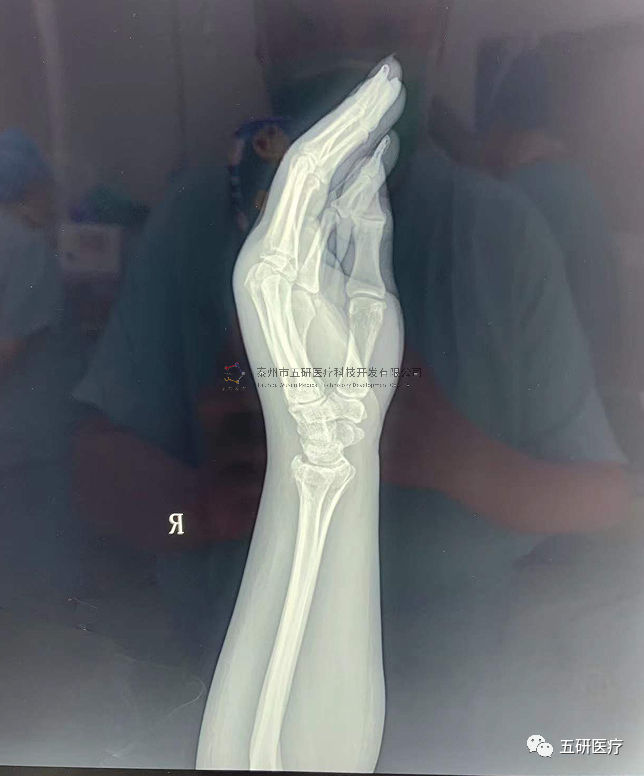

// 腕架

本病例由中國(guó)中醫(yī)科學(xué)院望京醫(yī)院骨綜科提供(術(shù)者:支架醫(yī)生常醫(yī)師)

【基本資料】患者,女,61歲

本病例腕架骨折。術(shù)前正側(cè)位片:右橈骨遠(yuǎn)端骨折。

1.png

采用常規(guī)方法固定,自掌骨尺側(cè),約基底稍偏遠(yuǎn)處穿入螺紋針。

1.webp.jpg

外架馬蹄環(huán)穿過(guò)骨針,更方便調(diào)整固定角度。